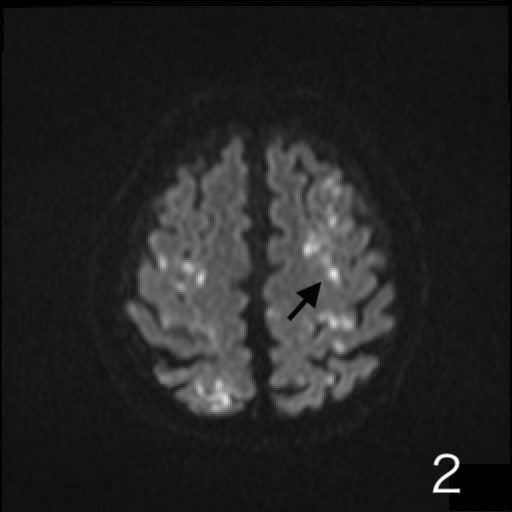

Abstract Image